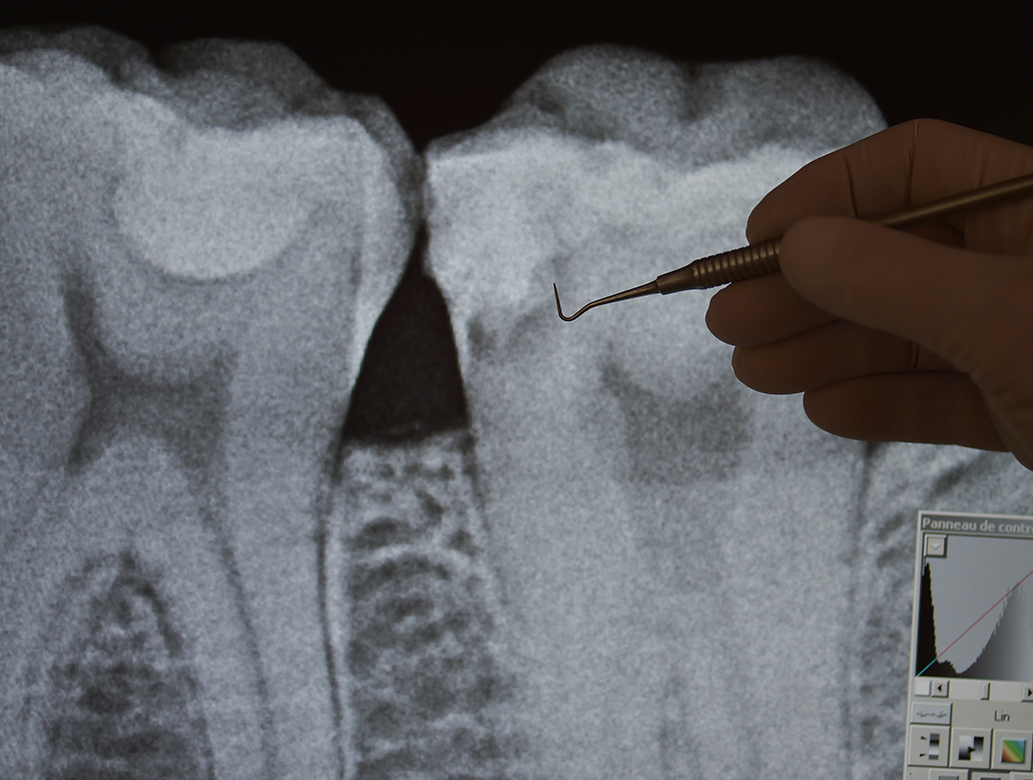

La radiología digital es el conjunto de técnicas para obtener imágenes radiológicas escaneadas en formato digital. La radiología digital se utiliza en medicina humana y veterinaria, odontología, pruebas no destructivas y de seguridad en que no es necesario tener el soporte en película.

- Obtener una mejor calidad de imagen gracias a las posibilidades que ofrece el filtrado digital;

- Facilitar el acceso a más información debido a una mejor resolución de contraste (el ojo sólo puede ver alrededor de 200 niveles de gris se realizan en las digitalizaciones entre 4000 (12 bits) y 65.000 (16 bits) niveles gris según los dispositivos, que se pueden convertir en niveles accesibles al ojo de una forma optimizada de acuerdo con la información que se desea;